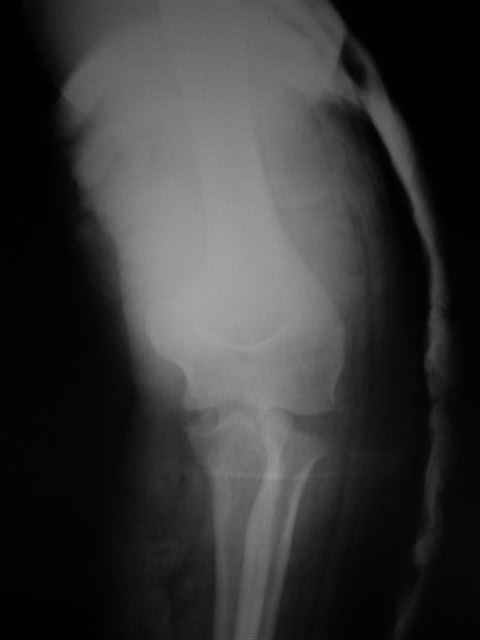

Вывих костей предплечья и перелом головки лучевой кости. |

Уважаемые коллеги!Помогите с источниками литературы по вопросу о сроках резекции головки лучевой кости и гетеротопической оссификации после вывиха костей предплечья. Необходимо ответить на жалобу, где больная просит возместитьматериальные затраты на лечения с лечащих врачей, которые участвовали влечении с 4.09.04 по 10.11.04, объясняет, что врачи нарушили стандарты леченияи поздно направили на оперативное лечение.История болезни, женщина 46 лет упала дома 4.09.04, получила заднелатеральныйвывих костей предплечья и перелом головки лучевой кости, под местной анестезиейвывих вправлен, на контрольной рентгенограмме соотношение отломков головкилучевой кости расценено, как удовлетворительное. Наложена задняя гипсовая шина.Лечение: холод, кетанов 3 дня, магнитотерапия, ЛФК пальцев, рентген контрольчерез 7 дней, с 8.09.05 наклофен 50 мг 2 раза в день. 11.09.04 на контрольной рентгенограмме состояние отломков прежнее. 30.09.04. Гипсовая шина снята через 26 дней. Лечение: ЛФК, массаж, электрофорезлидазой.9.10.04. В левом локтевом суставе сгибание 80, разгибание 120.19.10.04. Сгибание 80, разгибание 140, ротационные движения в пределах 10 гр.28.10.04. Сгибание 80, разгибание 150, ротационные движения в пределах 10 гр.10.11.04. На рентгенограмме локтевого сустава отмечается гетеротопическаяоссификация.Учитывая неэффективность консервативного лечения, больная направлена на оперативноелечение.Больная по собственным каналам уехала в г. Киев, где произведенарезекция головки лучевой кости, после операции развился неврит лучевого нерва.На данный момент больная продолжает лечение у нейрохирурга.-- С уважением,Анатолий Борзунов

А есть снимки?

Mozgounov> А есть снимки?

Во время встречи фотоаппарата не было, забрать снимки на время, муж больной снимки не разрешил.